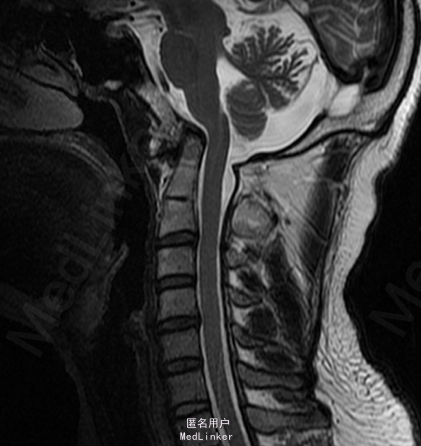

患者2年前无诱因出现后颈背部疼痛,呈胀痛性质,并伴有颈部及双上肢僵硬,休息后稍缓解,无头晕、恶心、呕吐等症状,就诊于其他医院,行MRI及颈部X片示:颅底凹陷症及寰枢椎脱位,建议患者手术治疗,患者要求暂行保守治疗,遂口服颈痛颗粒1包/tid、独一味胶囊3粒/tid、西乐葆200mg/bid,口服后症状未见明显缓解。6月前患者自觉颈背部疼痛发作频率增加,且疼痛时间延长及疼痛程度增加,同时伴右上肢麻木,并反复发作,为求手术治疗,患者来我院门诊,并以“颅底凹陷症 寰枢椎脱位”收入我科。

MRI及颈部X片示:颅底凹陷症及寰枢椎脱位

综上初步诊断:1、寰枢椎脱位;2、颅底凹陷症。